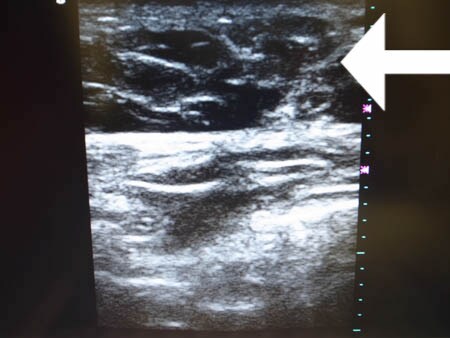

いつものように3Dタッチビュー(超音波)で

皮下脂肪層を評価してみましょう。

上腹部

↓ ↓ ↓

上の画像の部分の皮下脂肪層をつまんでみましょう。